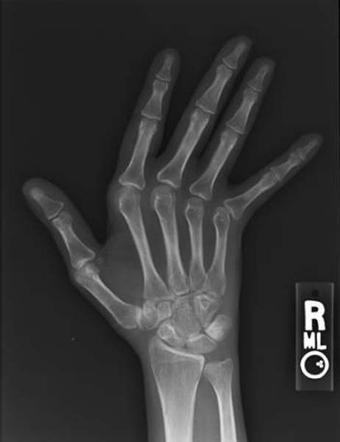

У больных системной красной волчанкой хронический воспалительный процесс в суставах кистей и периартикулярных тканях приводит к формированию вправляемых подвывихов межфаланговых и пястнофаланговых суставов, ульнарной девиации и амиотрофии, т.е. к развитию деформирующей артропатии кистей, или синдрома Жакку. Развивающиеся сгибательные контрактуры пальцев рук со временем могут приводить к необратимым нарушениям функции кистей, в результате чего больные становятся инвалидами даже при отсутствии тяжелого поражения висцеральных органов.

По себе наблюдаю очень легкую ульнарную девиацию (т е отклонение пальцев в сторону локтевой кости = мизинца = вбок), гипермобильность суставов и атрофию мышц. Если гадать по руке, то можно найти не только основные линии, а сетку из разнонаправленных складочек (линии жизни/судьбы итд - показатель функции мышц и суставов, направления сгибания ладони, а еще тургора и эластичности кожи).

Мои ревматологи описывают это все как "умеренная дефигурация кисти", но мне кажется, что это чересчур.